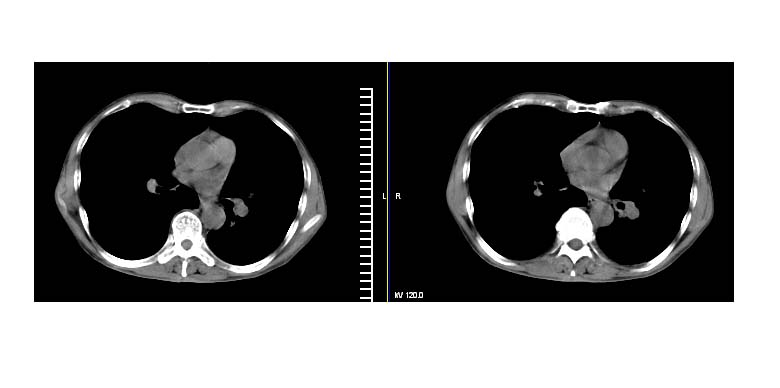

标题: CT11019:男性,66岁。发烧5-6天。治疗后无明显好转。 [打印本页]

标题: CT11019:男性,66岁。发烧5-6天。治疗后无明显好转。

左下肺中央型肺癌伴阻塞性肺炎\\肺不张可能性大,建议支纤镜检查.

1.左肺门似可见一小块影,由此考虑中央型肺ca并阻塞性肺炎改变;

2.左下叶背段肺tb(干酪性肺炎)?

3.单纯肺感染?建议进一步检查。

左下肺中心性肺癌伴下肺不张及周围阻塞性炎症

左下肺中央型肺癌伴阻塞性肺炎\\肺不张可能性大,建议支纤镜检查

左肺门下分增大见有结节影,基底干及分支显示不清,下叶体积缩小,呈片带状机磨玻璃样影显示。支持考虑左下肺中心型肺癌伴阻塞性肺炎及部分肺不张。建议纤支镜检查